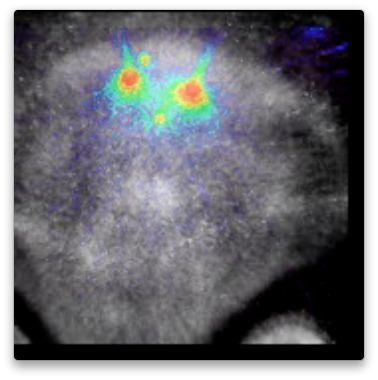

A natural stroke model in rabbits, in routine use in the laboratory Dr. Culp at UAMS, has been used for research into stroke progression and treatment. By addition of imaging to this model, the detailed progression of treatment of stroke has been measured. Clots formed from the rabbit’s blood were radiolabeled by 3D Imaging with F-18 (I-124 and Zr-89 labeling is equally possible, as well as labeling for SPECT with I-125 or I-123, or even fluorescent labeling; but the use of PET allowed quantitative measurement of clot dissipation during a two hour period including treatment.). The radiolabeled blood clots were used by Dr. Culp’s lab to create a natural stroke which was then treated. PET imaging before, during, and after treatment established that the clots were stable without treatment, degraded during treatment, and continued to degrade after treatment. These videos show the progression. In some only the PET scans are shown, so only the clots are visible, but are easily located and quantified. In others, an overlay of an FDG image is used to show the loacation of the brain and other soft tissues.

Videos show the field of view as it evolves in time, and with rotation to help visualize the 3D data and relative positions of the clots. Click on image to download and view the Videos.